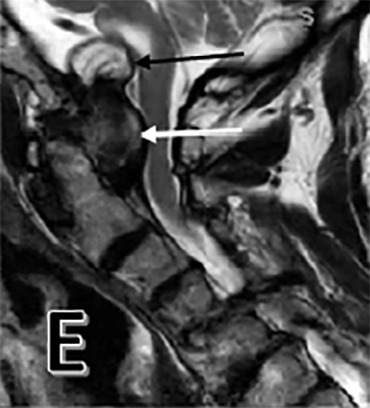

After his work-up was completed, the patient was found to have large odontoid pannus causing compression at the cranial cervical junction. We also noted a cyst associated with this pannus causing significant mass effect on the medulla (Figure 1 E). On MRI, this produced a T2 hyperintense signal at the medulla consistent with encephalomalacia, or medullary atrophy (Figure 1 A). The patient also had diffuse spondylosis, or degeneration, of the cervical spine along with central stenosis at the C4-5 and C5-6 level (Figure 1 C). Both an MRI of brain and CT angiogram were obtained and failed to reveal any other pathology. The posterior odontoid mass was found to be due to his rheumatoid arthritis.

The patient was followed up for two years. There was improvement in his motor weakness symptoms and he was eventually able to ambulate without an assisted device. Radiographic evaluation at the two-year follow-up mark showed marked reduction in the pannus and associated cyst with resolution of T2 hyperintense signal within the medulla (Figures 1 B, F). While there are reports in the surgical literature of smaller-sized pannus causing cervical spinal cord compression, we have been unable to identify any reports of such a large odontoid pannus with associated cyst and medullary compression.8